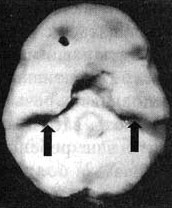

Трехмерное изображение нижней поверхности.